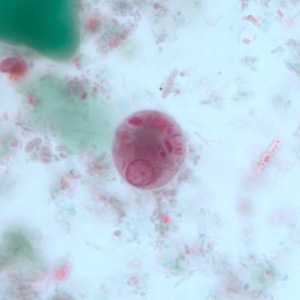

A 45-year-old pig farmer from rural Georgia presented to his health care provider with abdominal pain, cramps and diarrhea. Stool specimens were collected in polyvinyl alcohol (PVA) and 10% formalin for ova and parasite (O&P) examination. The objects in Figures A and B, which measured on average 90 micrometers in length, were observed in low numbers in formalin-concentrated wet mounts of the stool. The objects in Figures C and D, which measured on average 12 micrometers in diameter, were seen in moderate numbers on trichrome-stained slides prepared from the PVA-preserved stool. What is your diagnosis? Based on what criteria?

Figure D

This was a case of balantidiasis, caused by Balantidium coli (Figures A and B); also observed were cysts of Entamoeba polecki (Figures C and D). Diagnostic features included:

- uninucleate cysts of E. polecki (Figures D and E) containing a nucleus with a pleomorphic karyosome and evenly-distributed peripheral chromatin, and many irregularly-shaped chromatoid bodies, as well as being within the size range (11-15 micrometers) of the species.